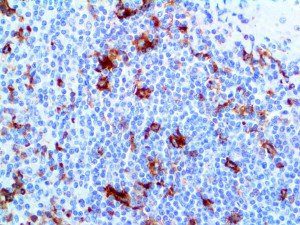

The first cytokines released are interleukin 1β (IL-1β) and tumor necrosis factor-α (TNF-α), which attract a variety of circulating white blood cells (WBCs) to the infection site, including neutrophils, monocytes, macrophages, and natural killer (NK) cells. This response, along with the antipathogenic chemicals released by these cells (i.e., complement), comprise the innate immune response. These cells directly attack the invading pathogen and also release additional cytokines, chief among them interleukin-1 and 6 (IL-6). IL-6 is essential for invoking the adaptive immune response, which calls T-cells, B-cells, and T helper (Th) cells to the infection site. IL-6 also stimulates further recruitment, proliferation and activation of macrophages.

It is the ICU physician who is most likely to witness one of the deadliest manifestations of the abnormal immunological response, the cytokine storm syndrome (CSS). This response is also referred to by some as the cytokine release syndrome (CRS). CSS is characterized by continuous activation and expansion of macrophage and lymphocyte populations, which secrete large amounts of cytokines, causing the cytokine storm. This massive cytokine release is akin to hemophagocytic lymphohistiocytosis (HLH) disease, a syndrome characterized by initial unchecked and persistent activation of cytotoxic T lymphocytes and NK cells.